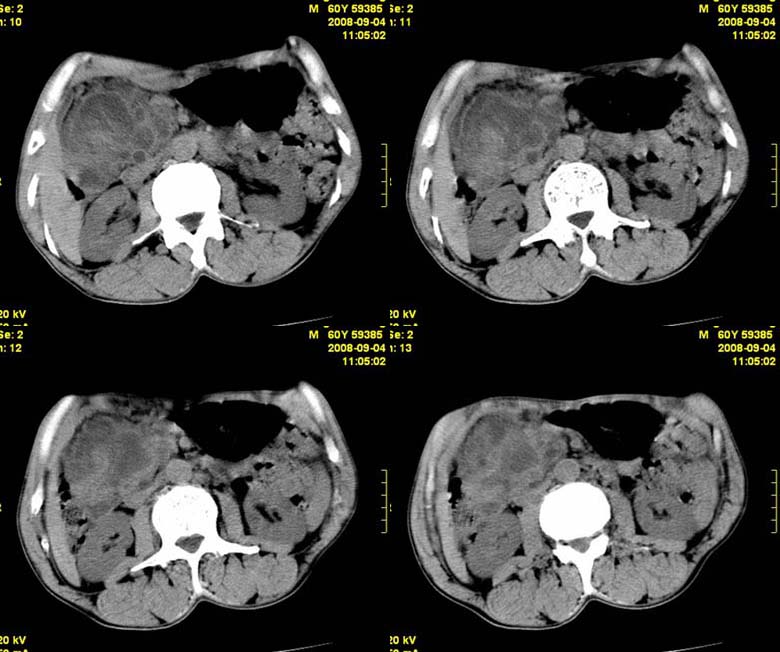

标题: CT15580:M60Y,胰腺病变,平扫+增强 [打印本页]

标题: CT15580:M60Y,胰腺病变,平扫+增强

患者,男, 60,既往有间歇腹痛病史多年,现右上腹痛,加重一月,伴右后背部疼痛,无黄疸,无发热。

胰头区增大,胰管明显扩张,不均匀强化,且与 周围结构不清,后背疼痛,考虑为胰腺头部胰腺癌。

胰头囊腺癌

以下是引用zsl6918在2008-9-5 21:21:00的发言:

考虑胰腺囊腺瘤或慢性胰腺炎

考虑胰腺囊腺瘤或慢性胰腺炎可能性大

支持

粘液性囊腺瘤

同意胰头部囊腺癌

胰头囊样增大不均匀强化,腺管扩张。结合病史首诊慢性胰腺炎、假性囊肿